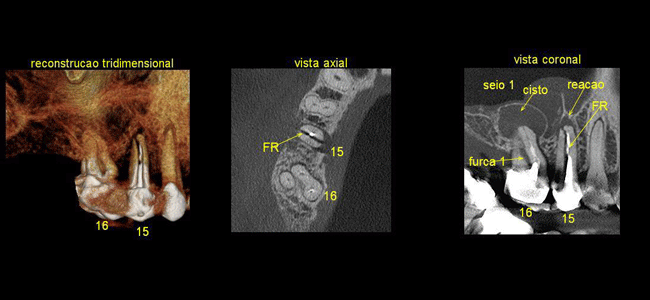

O nome Tomografia vem do grego – Tomos: Secção e Grafia: registro , ou seja, consiste no registro de secções ou “fatias” do corpo examinado pelo o uso dos raios X, e reconstruídas por softwares de computador. Por possuir este princípio e pelo fato de que esta obtenção se dá a partir de programas específicos de computador, recebeu o título de Computadorizada.